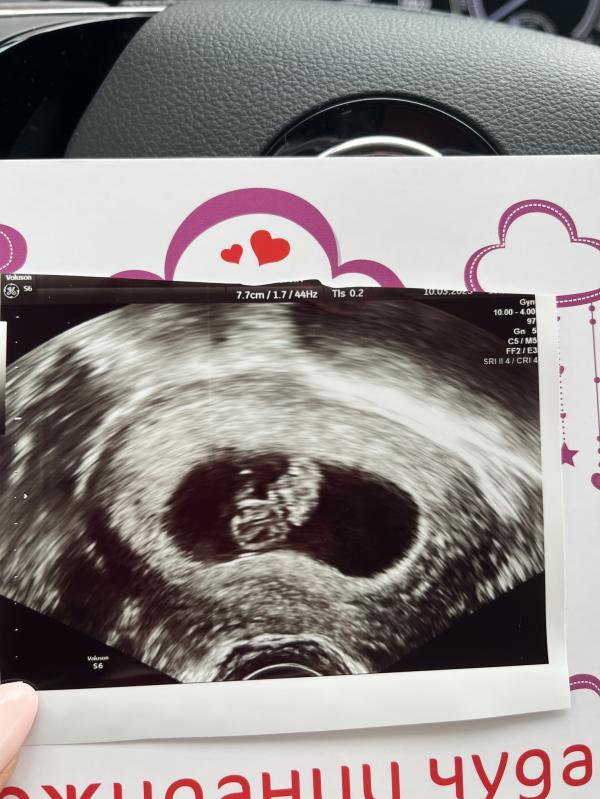

8,4 недели❤️ как же я переживала за это УЗИ… прошлая Б замерла как раз на сроке 8,6недель.

Сейчас все в порядке, сердечко бьется, КТР 23мм👌🏻